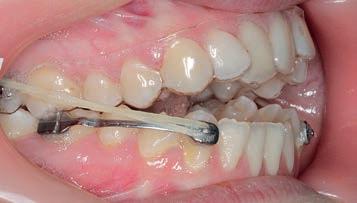

Motion Class III appliance bonded

Treatment commenced with the Motion Class III appliance bonded directly to the lower canines and first molars with 6 oz, ¼ intraoral elastics engaged for Class III traction to molar tubes bonded to the

Figs. 2a–c: Situation after 1 month of correction with Sagittal First approach.

upper second molars. An Essix .04 vacuum-formed retainer*** was employed in the upper arch for maximum anchorage.